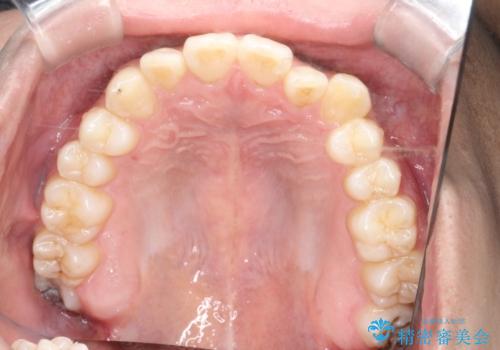

- 八重歯が気になるとのことでご来院されました。お口の中を確認すると、上の前歯がスペース不足で押し出され、少し前に出ている状態でした。抜歯せずに整えるため、奥歯を少しずつ後ろに動かしながら(遠心移動)、歯と歯の間をわずかに削るIPRを行ってスペースを作ることにしました。また、上下の噛み合わせを整えるために2級ゴム(エラスティック)を使用する方針を立てました。

マウスピースを段階的に交換しながら、奥歯を少しずつ後ろへ動かし、八重歯がきれいに並ぶよう調整しました。前歯の突出感を抑えるためにIPRを行い、スムーズに配列。さらに、2級ゴムを活用して噛み合わせも改善しました。治療後は、自然な歯並びになり、笑顔に自信が持てるようになったと喜んでいただきました。